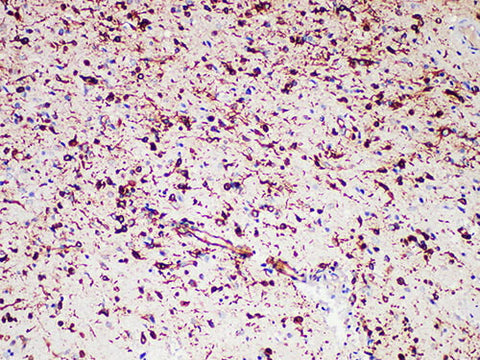

Nestin Monoclonal Antibody Stored at 2~8°C

Applications IHC-P

Tissue Specificity Glioma

Nestin is a 200kDa class Ⅵ intermediate filament protein that is mainly expressed in early embryonic neuroepithelial stem cells and during tendon and neuromuscular joint development. "Nestin is not specific for the central nervous system because it identifies not only the most primitive neuroepithelium but also other embryonic tissues." Nestin is expressed in almost all glioblastomas and melanomas (primary and metastatic), but it is not expressed in any metastatic carcinoma.